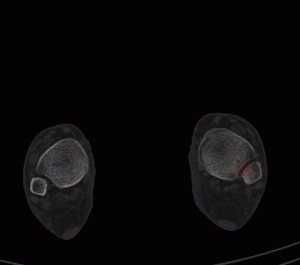

Aux temps angioscintigraphique et précoce :

Hypervascularisation avec hyperhémie tissulaire focale centrées sur les deux naviculaires, prédominant du côté gauche.

Au temps tardif et sur la SPECT-CT complémentaire :

A gauche, hyperfixation focale en regard d’une fragmentation de la partie latérale de l’os naviculaire, avec aspect condensé, et en « virgule » de l’os.

Pour mémoire, matériel de chirurgie d’hallux valgus, sans hyperfixation associée.

A droite, aspect relativement similaire avec hyperfixation focale du versant latéral du naviculaire, trame osseuse condensée et aspect en virgule.